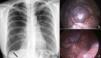

Paciente mujer de 41años de edad con antecedentes de neumotórax espontáneo derecho tratado con drenaje endotorácico. Es valorada en nuestro servicio por neumotórax espontáneo recidivante, objetivándose en la radiografía de tórax, además del neumotórax, una lobulación diafragmática (fig. 1a, flecha). Mediante abordaje videotoracoscópico se observó una hernia diafragmática congénita (fig. 1b) que se reparó con puntos sueltos de monofilamento, sin evidenciarse otras lesiones que pudieran justificar el origen del neumotórax (fig. 1c). La paciente fue dada de alta el cuarto día postoperatorio sin complicaciones.

a) Radiografía de tórax posterolateral en la que se objetiva un NTX derecho completo sin desplazamiento mediastínico. Se observa además la existencia de una lobulación diafragmática (flecha). b) Herniación diafragmática derecha vista por videotoracoscopia en la que se puede observar la cúpula hepática. c) Herniación cerrada con puntos sueltos de monofilamento.